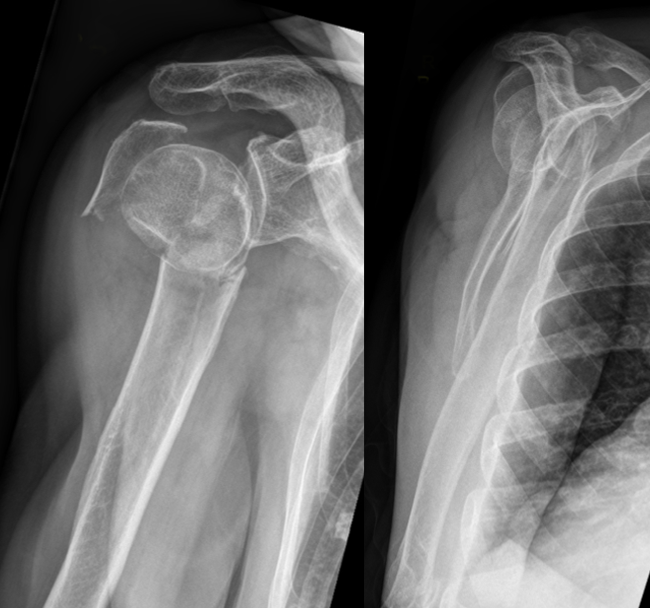

Pre-op

- 79 year-old female

- Stumbled and fell on floor in private home

- Dislocated proximal humeral 4-part fracture